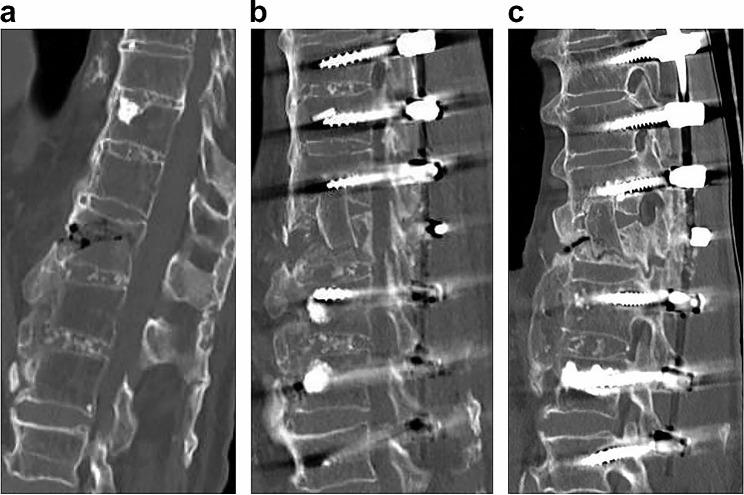

To achieve good bone fusion in anterior column reconstruction for vertebral fractures, not only bone mineral density (BMD) and bone metabolism markers but also lever arms due to bone bridging between vertebral bodies should be evaluated. However, until now, no lever arm index has been devised. Therefore, we believe that the maximum number of vertebral bodies that are bony and cross-linked with the contiguous adjacent vertebrae (maxVB) can be used as a measure for lever arms. The purpose of this study is to investigate the surgical outcomes of anterior column reconstruction for spinal fractures and to determine the effect of bone bridging between vertebral bodies on the rate of bone fusion using the maxVB as an indicator of the length of the lever arm.

The clinical data of 81 patients who underwent anterior column reconstruction for spinal fracture between 2014 and 2022 were evaluated. The bone fusion rate, back pain score, between the maxVB = 0 and the maxVB ≥ 2 patients were adjusted for confounding factors (age, smoking history, diabetes mellitus history, BMD, osteoporosis drugs, surgical technique, number of fixed vertebrae, materials used for the anterior props, etc.) and analysed with multivariate or multiple regression analyses. The bone healing rate and incidence of postoperative back pain were compared among the three groups (maxVB = 0, 2≦maxVB≦8, maxVB ≧ 9) and divided by the maxVB after adjusting for confounding factors.

Patients with a maxVB ≥ 2 had a significantly higher bone fusion rate (p < 0.01) and postoperative back pain score (p < 0.01) than those with a maxVB = 0. Among the three groups, the bone fusion rate and back pain score were significantly higher in the 2≦maxVB≦8 group (p = 0.01, p < 0.01).

Examination of the maxVB as an indicator of the use of a lever arm is beneficial for anterior column reconstruction for vertebral fractures. Patients with no intervertebral bone bridging or a high number of bone bridges are in more need of measures to promote bone fusion than patients with a moderate number of bone bridges are.